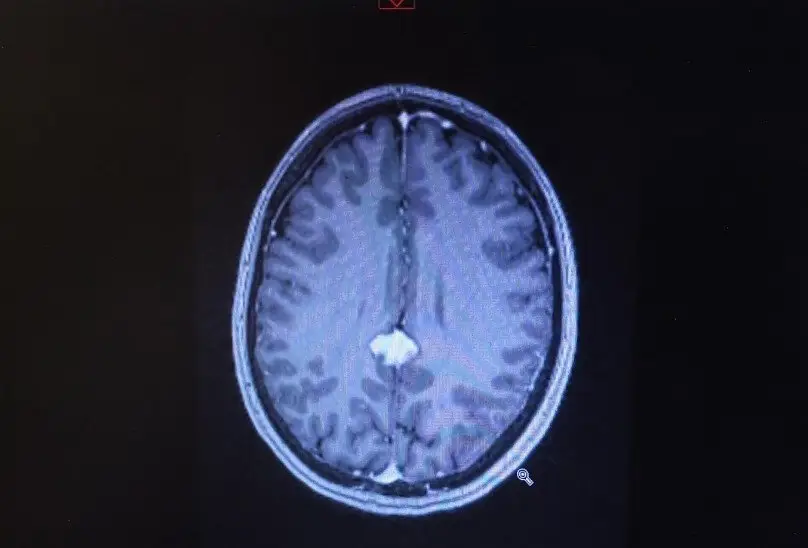

Technically, April had been diagnosed with a posterior falcine meningioma, a low-grade tumour which is located deep in the centre of her brain.

Because of this factor, the mum - who has one teenage daughter, Abby - was placed on watch and wait, and instructed to go for brain scans every six months.

By the end of 2022, however, the tumour had increased in size, leaving doctors with no option other than stereotactic radiotherapy, which seeks to minimise the damage the mass inflicts onto surrounding cells.

Not only did she have a mass on her brain, but doctors could tell straight away that surgery upon the tumour was no longer an option, due to its positioning.